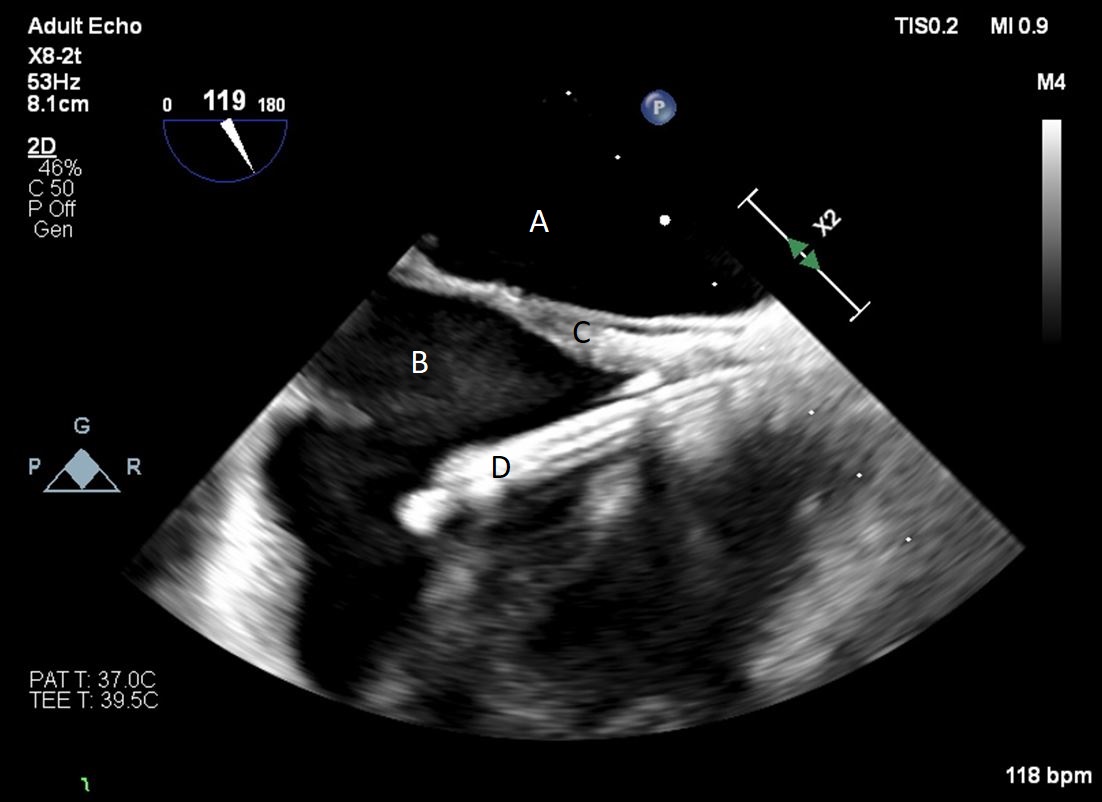

Both TTE and TEE can help with ideal positioning of the Impella (Figs. 5,6). The distance from the aortic valve to the Impella inlet should be measured. This should ideally be 3.5–4 cm for all Impella devices except for the Impella 5.5 for which it is 5 cm [15] (Fig. 7). The outlet should be 1.5–2 cm above the sinuses of Valsalva. The catheter should be angled towards the LV apex and away from the septum and mitral valve. The positioning of both the inlet in the LV cavity and the outlet above the aortic valve should be confirmed. Color flow doppler imaging can help confirm this positioning as a mosaic pattern will be visualized near the inlet and outlet ports on spectral doppler (Fig. 8). Real-time 3D echocardiography can also be used to help in visualizing Impella positioning relative to other anatomical structures (Fig. 9). After placement of the Impella, the aortic and mitral valves should be interrogated for any new or worsening regurgitation or dysfunction [16]. TEE can also help identify additional complications of Impella placement including pericardial effusion or LV free wall rupture [17].

Fig. 6.A midesophageal long axis view zoomed up on the aortic valve demonstrating the Impella traversing an open aortic valve. (A) Impella. (B) Ascending aortic root.

Fig. 7.A parasternal long axis view on a transthoracic echocardiogram. The distance from the Impella inlet to the aortic valve is measured and noted to be 3.9 cm. (A) LV Cavity. (B) Impella. (C) Ascending aortic root.